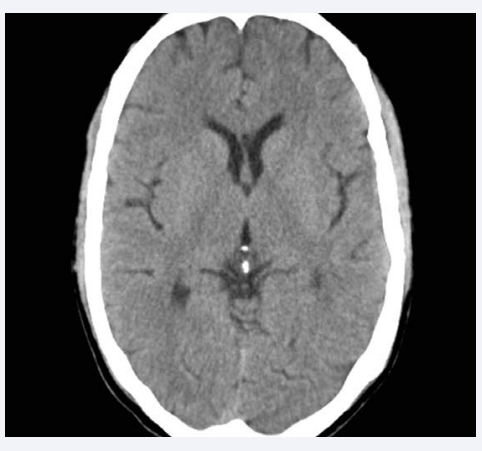

For determining and defining prevalence of normal and abnormal CSP we used the criteria that had been used in previous studies [8,18-20]. In these studies any CSP equal to or greater than 6 mm in length had been defined as abnormally large (Picture 1 & 2). CT scans of all patients and controls were reviewed, without knowledge of the diagnostic group by a neuroradiologist and a psychiatrist trained in neuroanatomy. Each rating was assigned on the basis of a consensus between the two examiners.

C.T. scan of an alcohol dependent patient showing abnormal  CSP (Length 7.0mm, Width 2.8mm, Width of septum 1.6mm)

Figure 1: C.T. scan of an alcohol dependent patient showing abnormal CSP (Length 7.0mm, Width 2.8mm, Width of septum 1.6mm)

Abbreviation: CSP: Cavum Septum Pellucidum